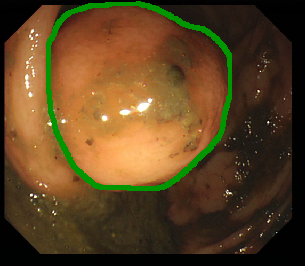

Figure 1: Polyp visual aspects have a wide variety in terms of shape and color. Four different polyps sampled from the different databases considered in this work: (a) Kvasir-Seg [19], (b) CVC-ClinicDB [5], (c) CVC-ColonDB [4], (d) ETIS [29].

The large bowel within the human gastrointestinal tract can be affected by different diseases, among which, Colorectal Cancer (CRC) is particularly concerning. CRC represents the second most common cancer type in women and third most common for men [15]. Gastro-intestinal polyps are known precursors of this type of cancer [34], being present in almost half of the patients over 50 undergoing screening colonoscopies [31]. This kind of lesions show a wide range of shapes and visual appearances, as shown in Fig. 1, turning its identification and segmentation into a challenging problem.